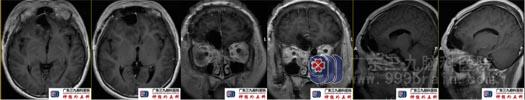

术前头颅MRI右侧额叶底部镰旁示一大小约37mm×25mm×30mm的团块状不均匀等长混杂T1、混杂等长T2异常信号影,Flair序列呈稍高、低混杂信号影,增强扫描后呈类环形强化,局部稍突入右侧筛窦内,周围示斑片状Flair序列高信号影。ADC图呈高、低混杂信号影。MRS示病变内可见明显升高的Lip峰,NAA及Cho、Cr峰均未见显示。提示右侧额叶底部镰旁病变,其内存在明显坏死,待排成人型弥漫性胶质瘤(或)不典型炎性肉芽肿病变。